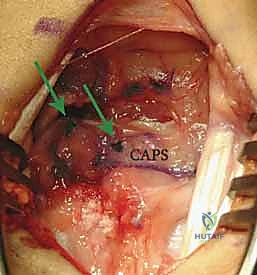

Once the capsule is reflected, the devastating pathology of the SLIL disruption is immediately apparent. We systematically inspect the radiocarpal and midcarpal articular surfaces to confirm the absence of advanced chondromalacia.

Observe the classic DISI deformity. The scaphoid is severely flexed, and the lunate is extended. The complete disruption of the SLIL is evident, leaving a yawning gap between the two carpal bones.

We meticulously debride the interposed hematoma, synovitis, and any frayed, non-viable ligamentous edges using a small rongeur and a motorized shaver. Typically, the dorsal SLIL avulses from its scaphoid footprint, leaving a robust stump attached to the lunate.

This high-magnification view clearly demonstrates the scaphoid on the left and the viable SLIL stump remaining attached to the lunate on the right, grasped securely by forceps.